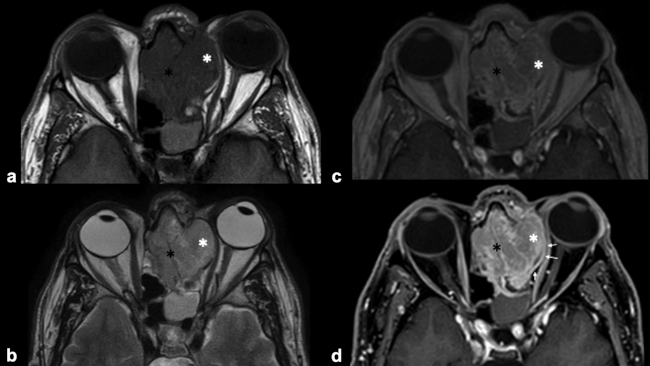

La RM es la prueba de imagen de elección para evaluar los detalles de la extensión y la estadificación locorregional del tumor. La RM es superior a la TC para determinar el grado de afectación del tejido blando (►Fig. 9) con una mejor evaluación de la afectación intracraneal (►Figs.10,11,12,13,14), orbital (►Figs.14y15), de la base del cráneo y la invasión perineural.53,54 La RM tiene un valor añadido para distinguir la afectación dural de la del parénquima cerebral (►Fig. 12).55 En la RM, el NBO aparece hipointenso respecto a la sustancia gris en imágenes ponderadas en T1 y de isointenso a hiperintenso en las imágenes ponderadas en T2 (►Figs.10,11,12,13,14,15).56 Muestra un realce homogéneo, excepto en áreas con hemorragia o necrosis. Además, permite diferenciar las secreciones retenidas del tumor, al ser estas hiperintensas ponderadas en T2.53,55 Los hallazgos de imágenes clásicos incluyen una masa “en forma de mancuerna” que se extiende a través de la placa cribiforme (►Fig. 12), con la parte estrecha a nivel de la placa. Los quistes tumorales periféricos (►Figs.5b,12,14,16) y las calcificaciones moteadas son bastante característicos de NBO.1

Las secuencias de RM con saturación de la grasa ayudan a diferenciar el tumor de la grasa orbital y los músculos. Un margen suave de la interfaz tumor-grasa sugiere que la lesión está contenida en la fascia periorbital (►Fig. 15), mientras que un margen irregular favorece la invasión franca de la órbita.35,49,57 Sin embargo, el diagnóstico definitivo de invasión de la duramadre y los tejidos periorbitarios solo es posible en la cirugía.49